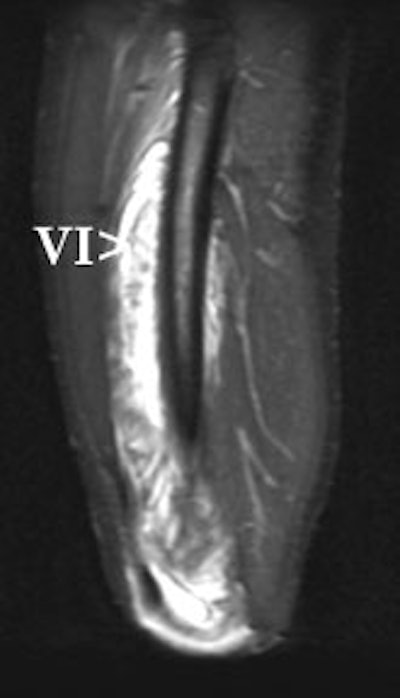

| Same patient, sagittal MRI, FSEIR. Arrows point to the vastus intermedius. Just as on the ultrasound, focal fluid collections surrounded by diffuse muscle edema are visible. |

The protocol for the MR scan included images in the axial plane, T2-weighting, fast spin echo (FSE), and fat saturation. As with the ultrasound, focal fluid collections were surrounded by diffuse muscle edema.